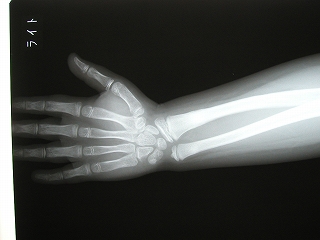

‰E‘O˜rœœÜ

@@”N—î@@8Î@—«

@@•‰“ú@•½¬14”N7ŒŽ27“ú

62Ҝ΋

œÜÇ—á